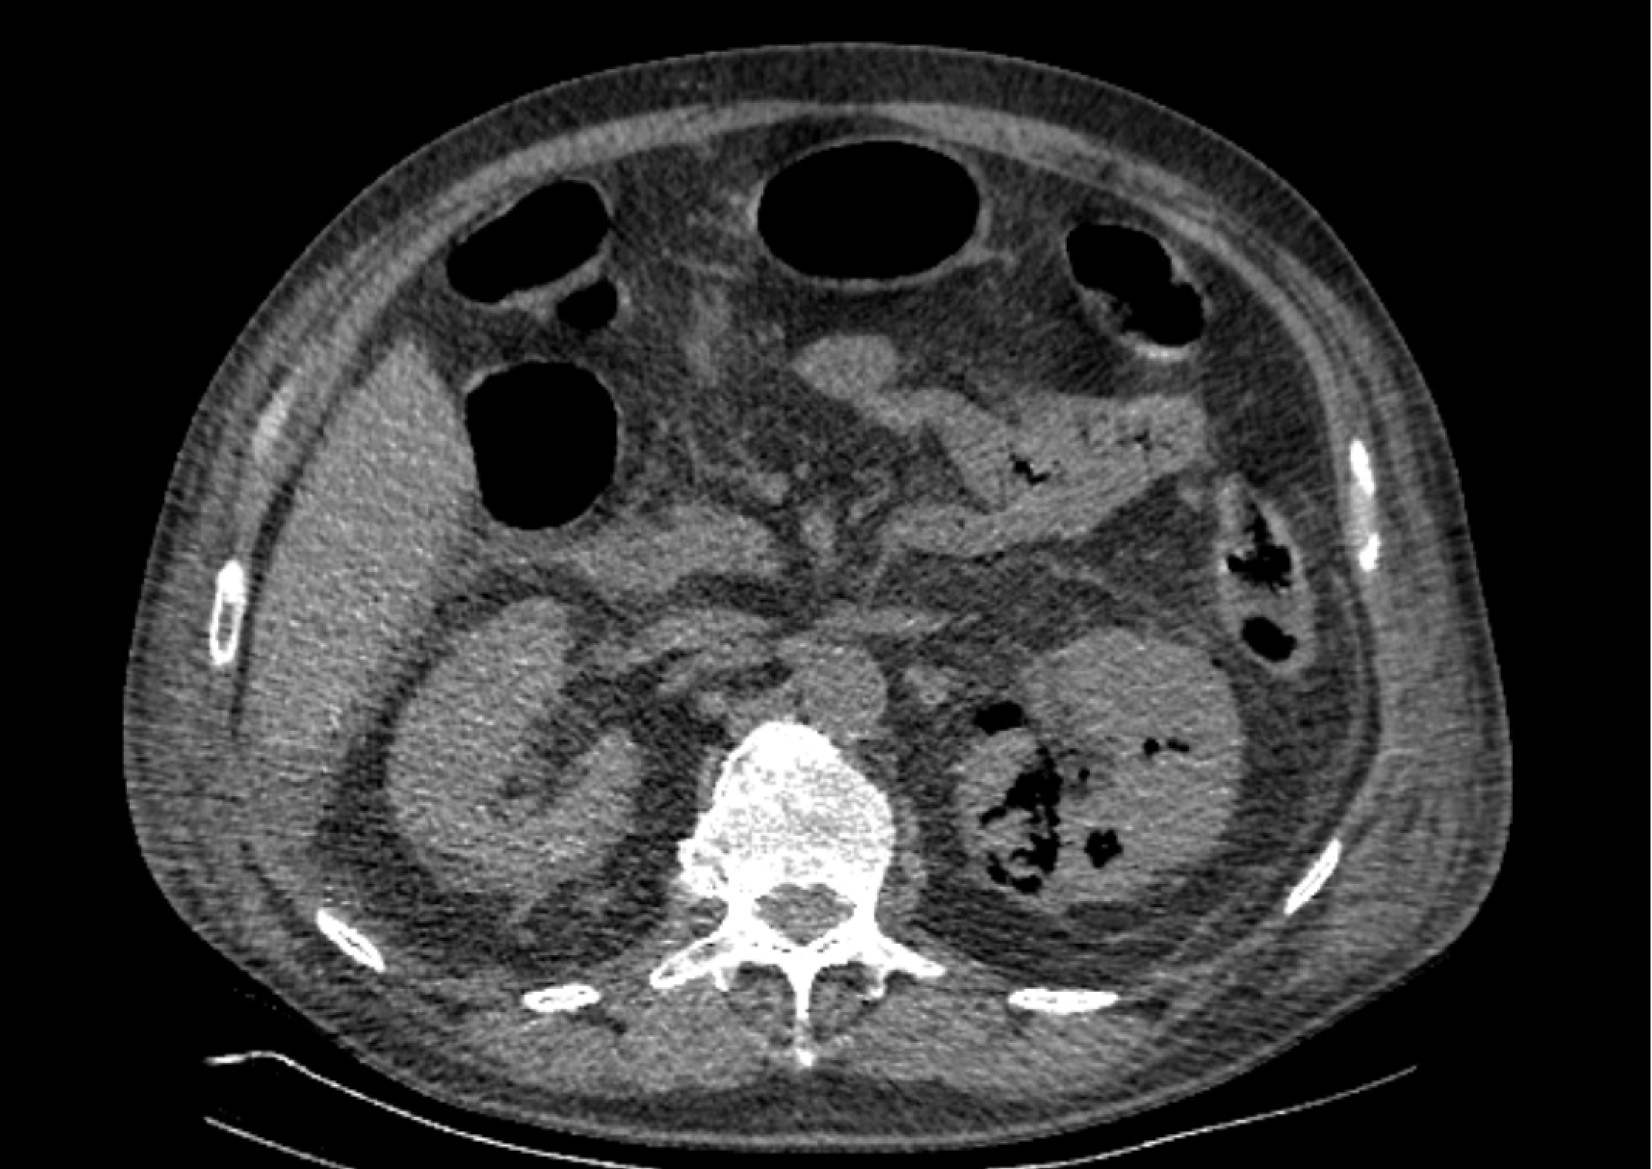

На следующий день состояние пациента оставалось тяжелым, с отрицательной динамикой, креатинин сыворотки возрос до 735,2 ммоль/л, Появились жалобы на слабость, тошноту. При осмотре: живот мягкий, вздут по всем отделам, при пальпации болезненный. Область почек не изменена, при пальпации безболезненна, патологических изменений в области почек не выявлено. Симптом поколачивания отрицательный билатерально. При УЗИ были обнаружены плевральный выпот по 300–400 мл с каждой стороны, гепатомегалия, увеличение размеров селезенки, асцит. Кроме того, в обеих почках были визуализированы тени, характерные для конкрементов. По данным компьютерной томографии (КТ) конкрементов не обнаружено, но в лоханке, на всем протяжении левого мочеточника и, частично, в правом мочеточнике, а также в мочевом пузыре визуализировался газ (рис. 1–6).

Рис. 6. Компьютерная томография органов брюшной полости, забрюшинного пространства, органов малого таза. Газ в верхнем полюсе левой почки